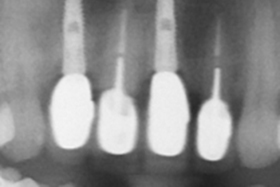

治療前,X光片及口內照片。

舊牙冠拆除後,術後X光片。